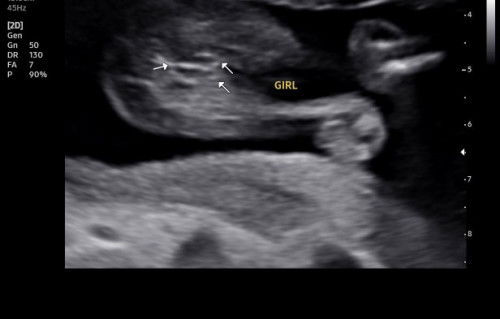

gender scan 2d

nak tanya klau mcm ni comfirm ke boboi

mommy MCM ni 💯 girl ke ?.. Dr cakap 50-60% girl ..

comfirm Boboi awak😍

instinct dr awal mmg rasa boy . scan 23 weeks doc kata boy . so harap kluar nnt pun confirm boy